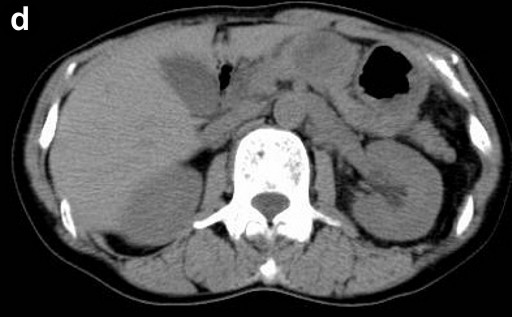

A 66-year-old Japanese woman was admitted to our hospital with a pancreatic tumor indicated in medical examinations. There was no remarkable past history of disease. No inherited factors or marked diseases in her family were noted. On admission, she had no complaints, and physical examinations and laboratory data revealed no noticeable abnormalities. Serum levels of CA 19-9 and s-pancreas-1 (pancreatic associated) antigen were within the normal range. Magnetic resonance imaging (MRI) revealed a mass, 3 cm in diameter, in the body of the pancreas, showing hypointensity on T1-weighted images, marked enhancement after gadolinium diethylenetriaminepenta acetic acid (Gd-DTPA) administration, and mixed hypo- and hyperintense patterns on T2-weighted images (Figure 1abc). Magnetic resonance cholangiopancreatography (MRCP) and endoscopic retrograde cholangiopancreatography (ERCP) showed no abnormal findings. The results of bacterial cultures of the pancreas juice were negative. Computed tomography (CT) revealed a 3 cm solid and cystic tumor within the body of the pancreas, with high resorption CT levels of the cystic components (Figure 1d). Contrast-enhanced CT showed partial enhancement of the solid components, and the main pancreatic duct was not involved in the tumor. Ultrasonography (US) and endoscopic ultrasonography (EUS) revealed a 3 cm solid and cystic tumor with low echoic margins in the body of the pancreas (Figure 2a). Contrast-enhanced US with Levovist® (Bayer Schering, Berlin, Germany) showed partial enhancement of the solid components (Figure 2b). Angiography showed no abnormal findings. From these imaging findings, mucinous cystic neoplasms or acinar cell tumors were considered.

Figure 2. a. US reveals a solid and cystic tumor with low echoic margin in the body of the pancreas. b. Contrast-enhanced US with Levovist® (Bayer Schering, Berlin, Germany) shows partial enhancement at the solid component. |

The solid and cystic pattern observed on CT was also seen with US, in which hypoechoic and/or cystic findings were noted in a high percentage of cases. However, the details of the solid components were revealed more clearly by US as compared to CT or MRI. Moreover, in the present case, contrast-enhanced US with Levovist® (Bayer Schering, Berlin, Germany) showed partial enhancement at the solid component.